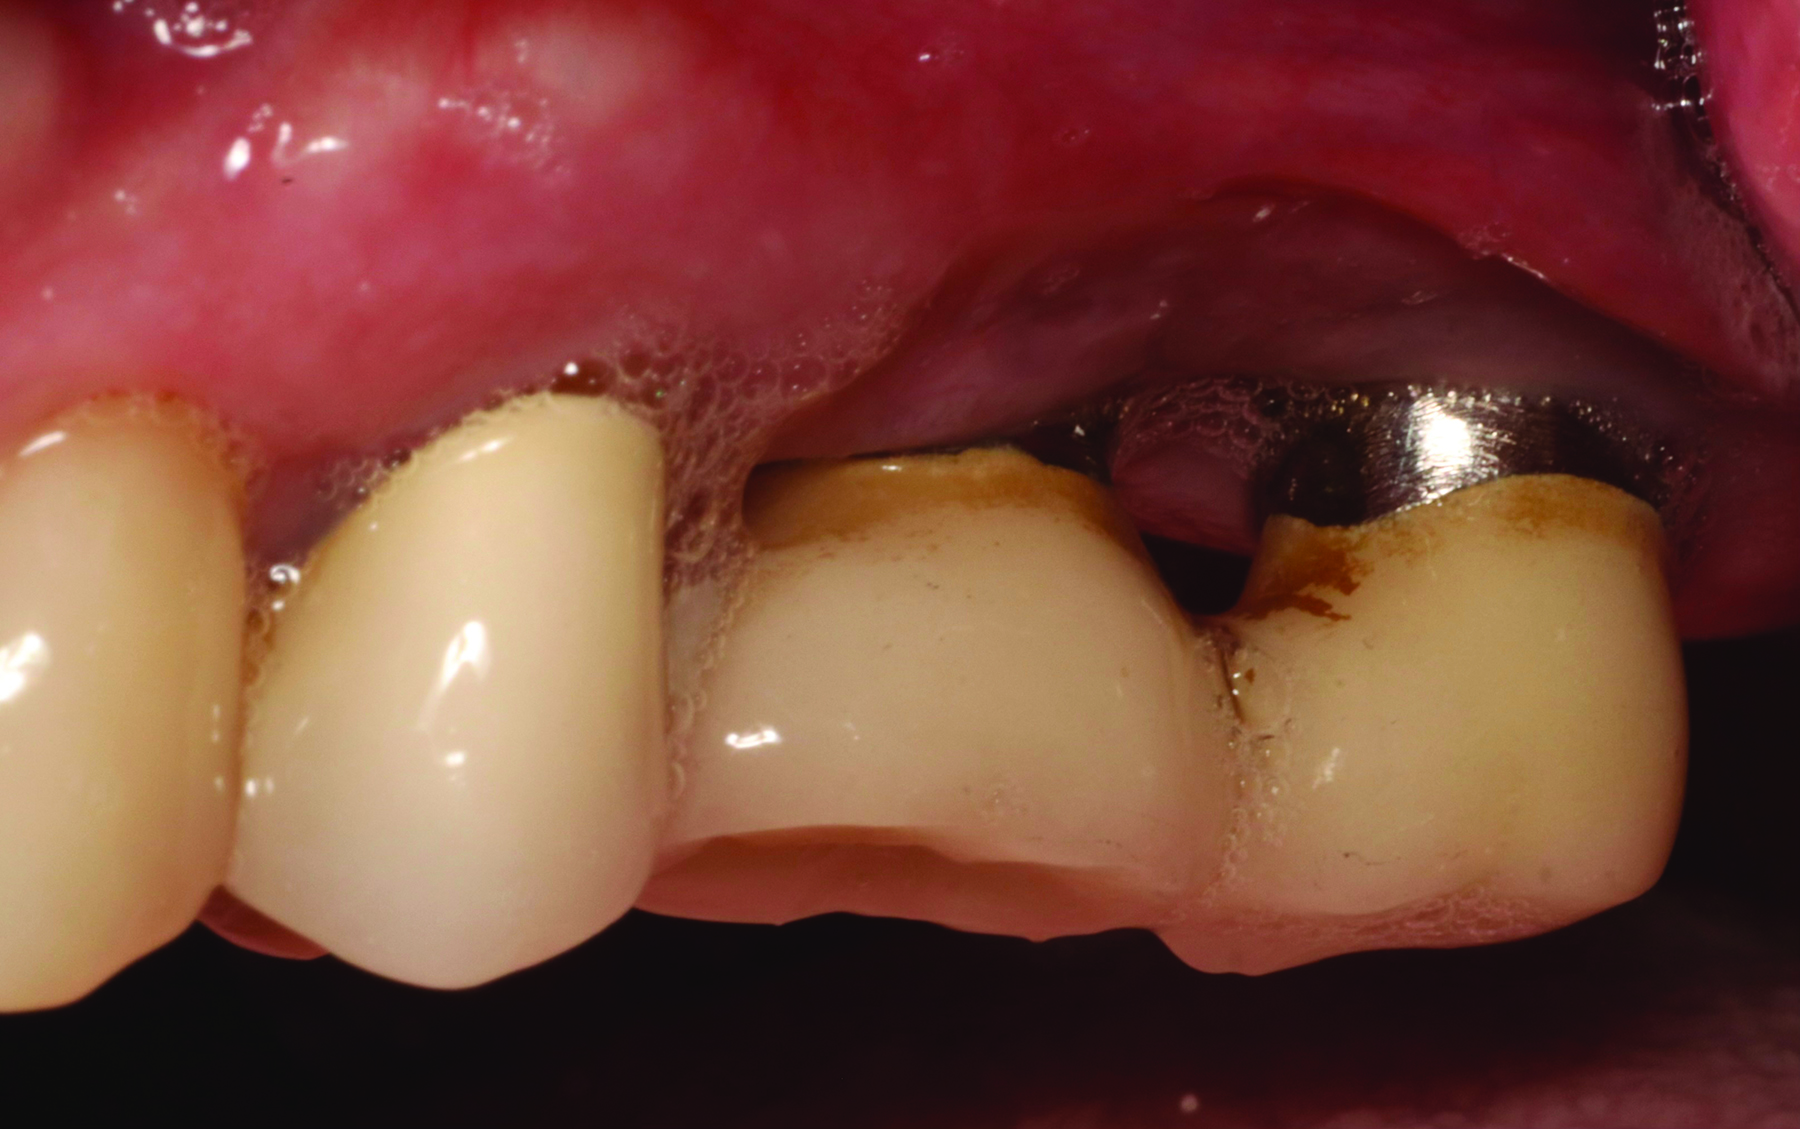

Fig 5 and Fig 6. Pre- (Fig 5) and post-treatment (Fig 6) photographs of a patient who received resective implant surgery to assess peri-implantitis at sites Nos. 14 and 15. Note the improved cleansability of the implants after surgery that opened the embrasure (Fig 6). The patient was placed on 3-month supportive peri-implant care post-surgery.

Figure 5